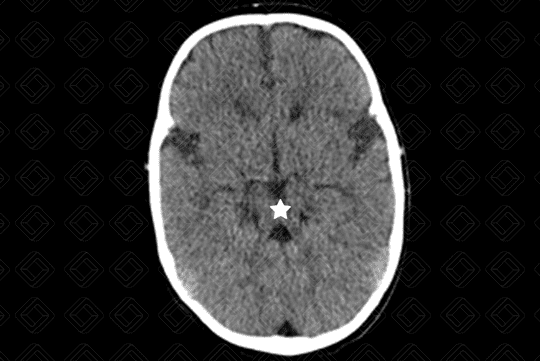

Descrição da lesão: Imagem de tomografia computadorizada do crânio evidenciando a presença de pedúnculos cerebelares superiores espessados e hipoplasia do vérmis, o que leva ao clássico sinal do "dente molar" no corte axial (asterisco).

Síndrome de Joubert: Também conhecida como malformação do dente molar, trata-se de anomalia autossômica recessiva caracterizada por hipoplasia do vérmis cerebelar e proeminência dos pedúnculos cerebelares superiores.

• Tomografia computadorizada do crânio: O bservamos o verme cerebelar fendido e o 4º ventrículo apresenta configuração em "asa de morcego";

• Ressonância magnética do crânio: F enda vermiana, aparência do "dente molar". Pedúnculos cerebelares superiores paralelos, proeminentes e no mesmo plano (raízes molares). Em alguns casos, pode cursar com mielinização anormal.